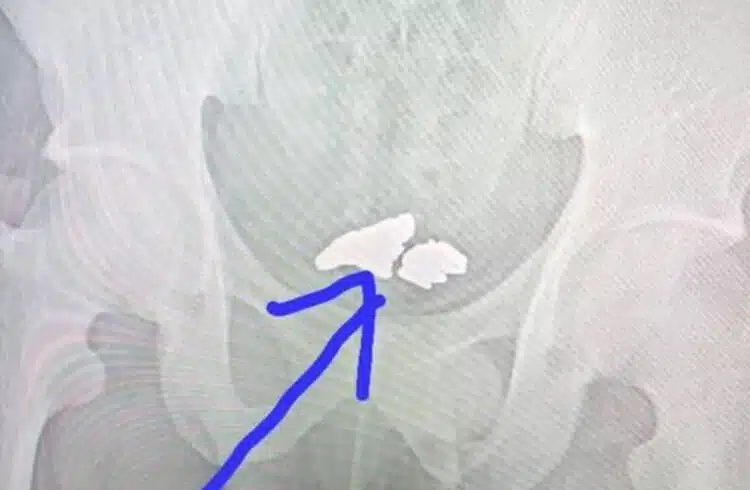

Крадецът бил откаран в местна болница, където с помощта на ултразвук лекарите открили 81 грама злато в тялото му. Операция обаче не се наложи. На работика му бяха дадени специални средства, благодарение на които металът след известно време излезе от тялото му по естествен път.